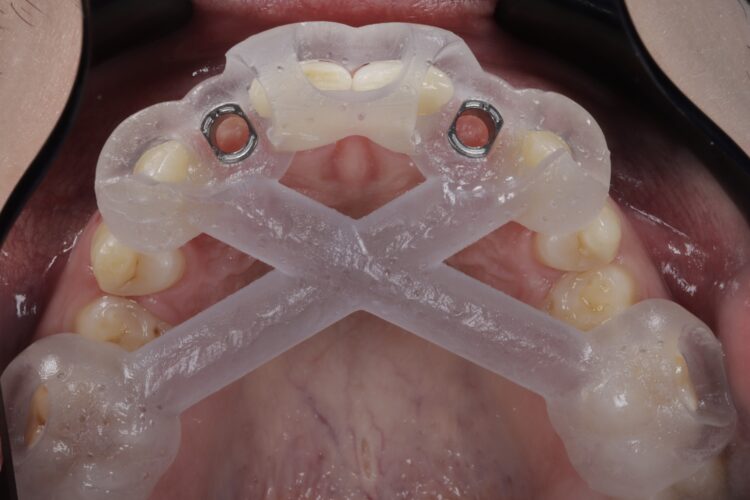

On the day of surgery, a split-thickness envelope flap was raised. Two CONELOG® Progressive-Line implants were placed through the surgical guide in the pre-determined lateral incisor positions. Soft tissue augmentation was performed simultaneously with the implant placement, and the site was sutured and closed without tension. The implants were immediately loaded using provisional crowns that were pre-fabricated in the lab.